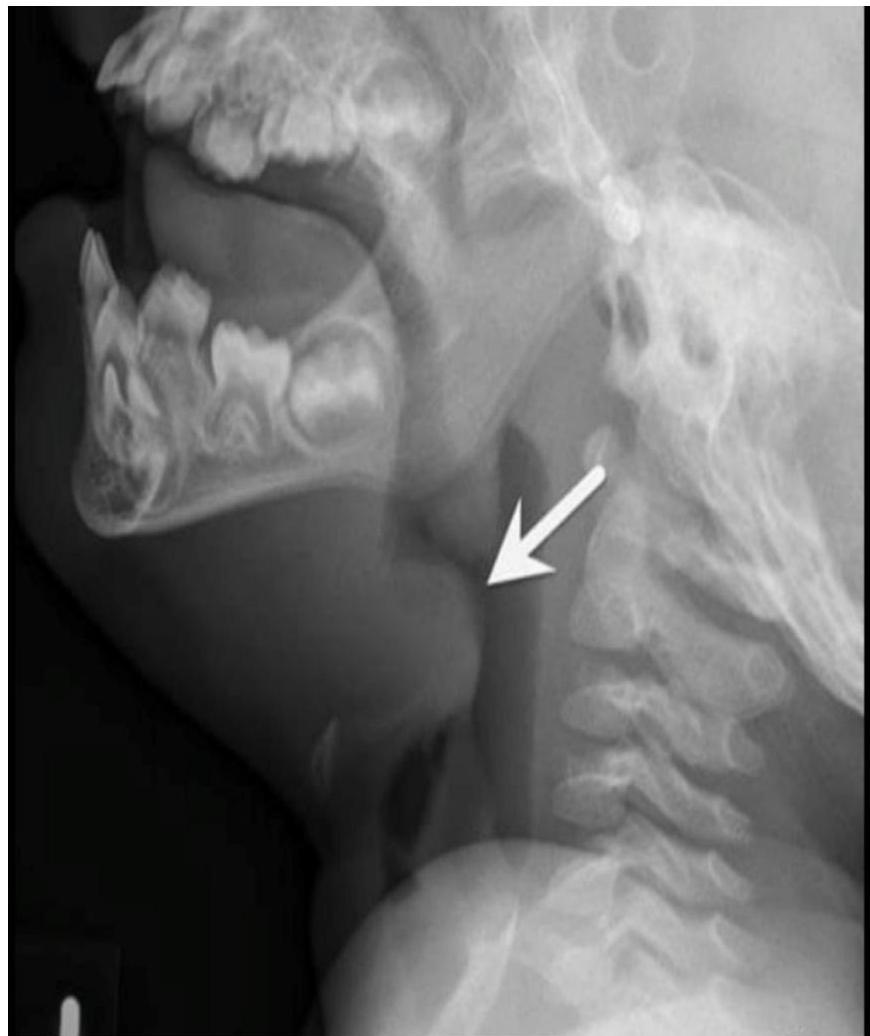

- Soft-tissue Lateral Neck Radiographs:

- Portable if possible.

- Positive in 80% of cases.

- Feature: An enlarged epiglottis protruding from the anterior wall of the hypopharynx (the “thumb sign”).

- Other findings: Thickened aryepiglottic folds, loss of vallecular air space, distended hypopharynx.

- X-ray: Look for the thumbprint sign.